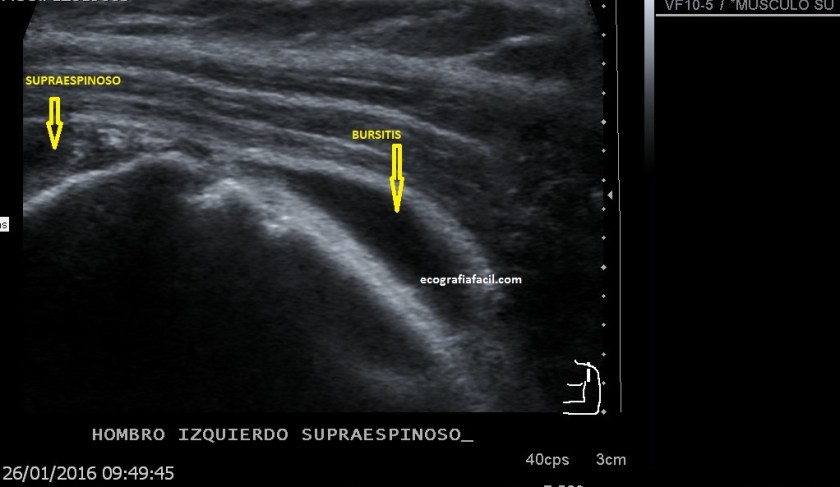

Si tu lo quieres estudiar en un corte transverso o eje corto del tendón verás como muestra de normalidad la imagen número 1. Semiológicamente es muy agradecido. Ves el tendón ovalado, hiperecogénico reposado en la corredera bicipital. El ligamento transverso humeral, hiperecogénico y lineal, anterior a la estructura tendinosa que descansa en la corredera.